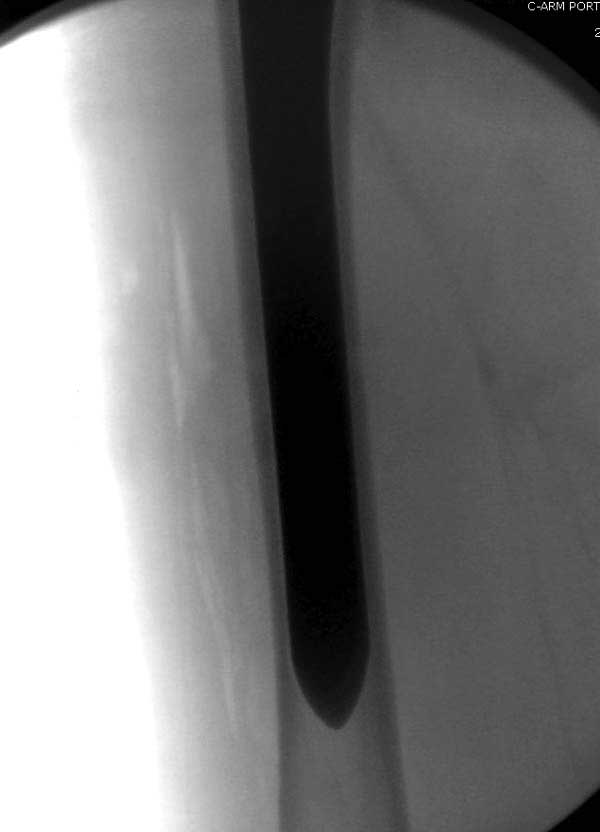

Повторно поступает после двух с половиной лет, где обнаруживается перелом на второй стороне. Немного сложно, но для фиксации выбрали Antegrade InterTan Smith Nephew Nail и с момента фиксации более 3х мес.